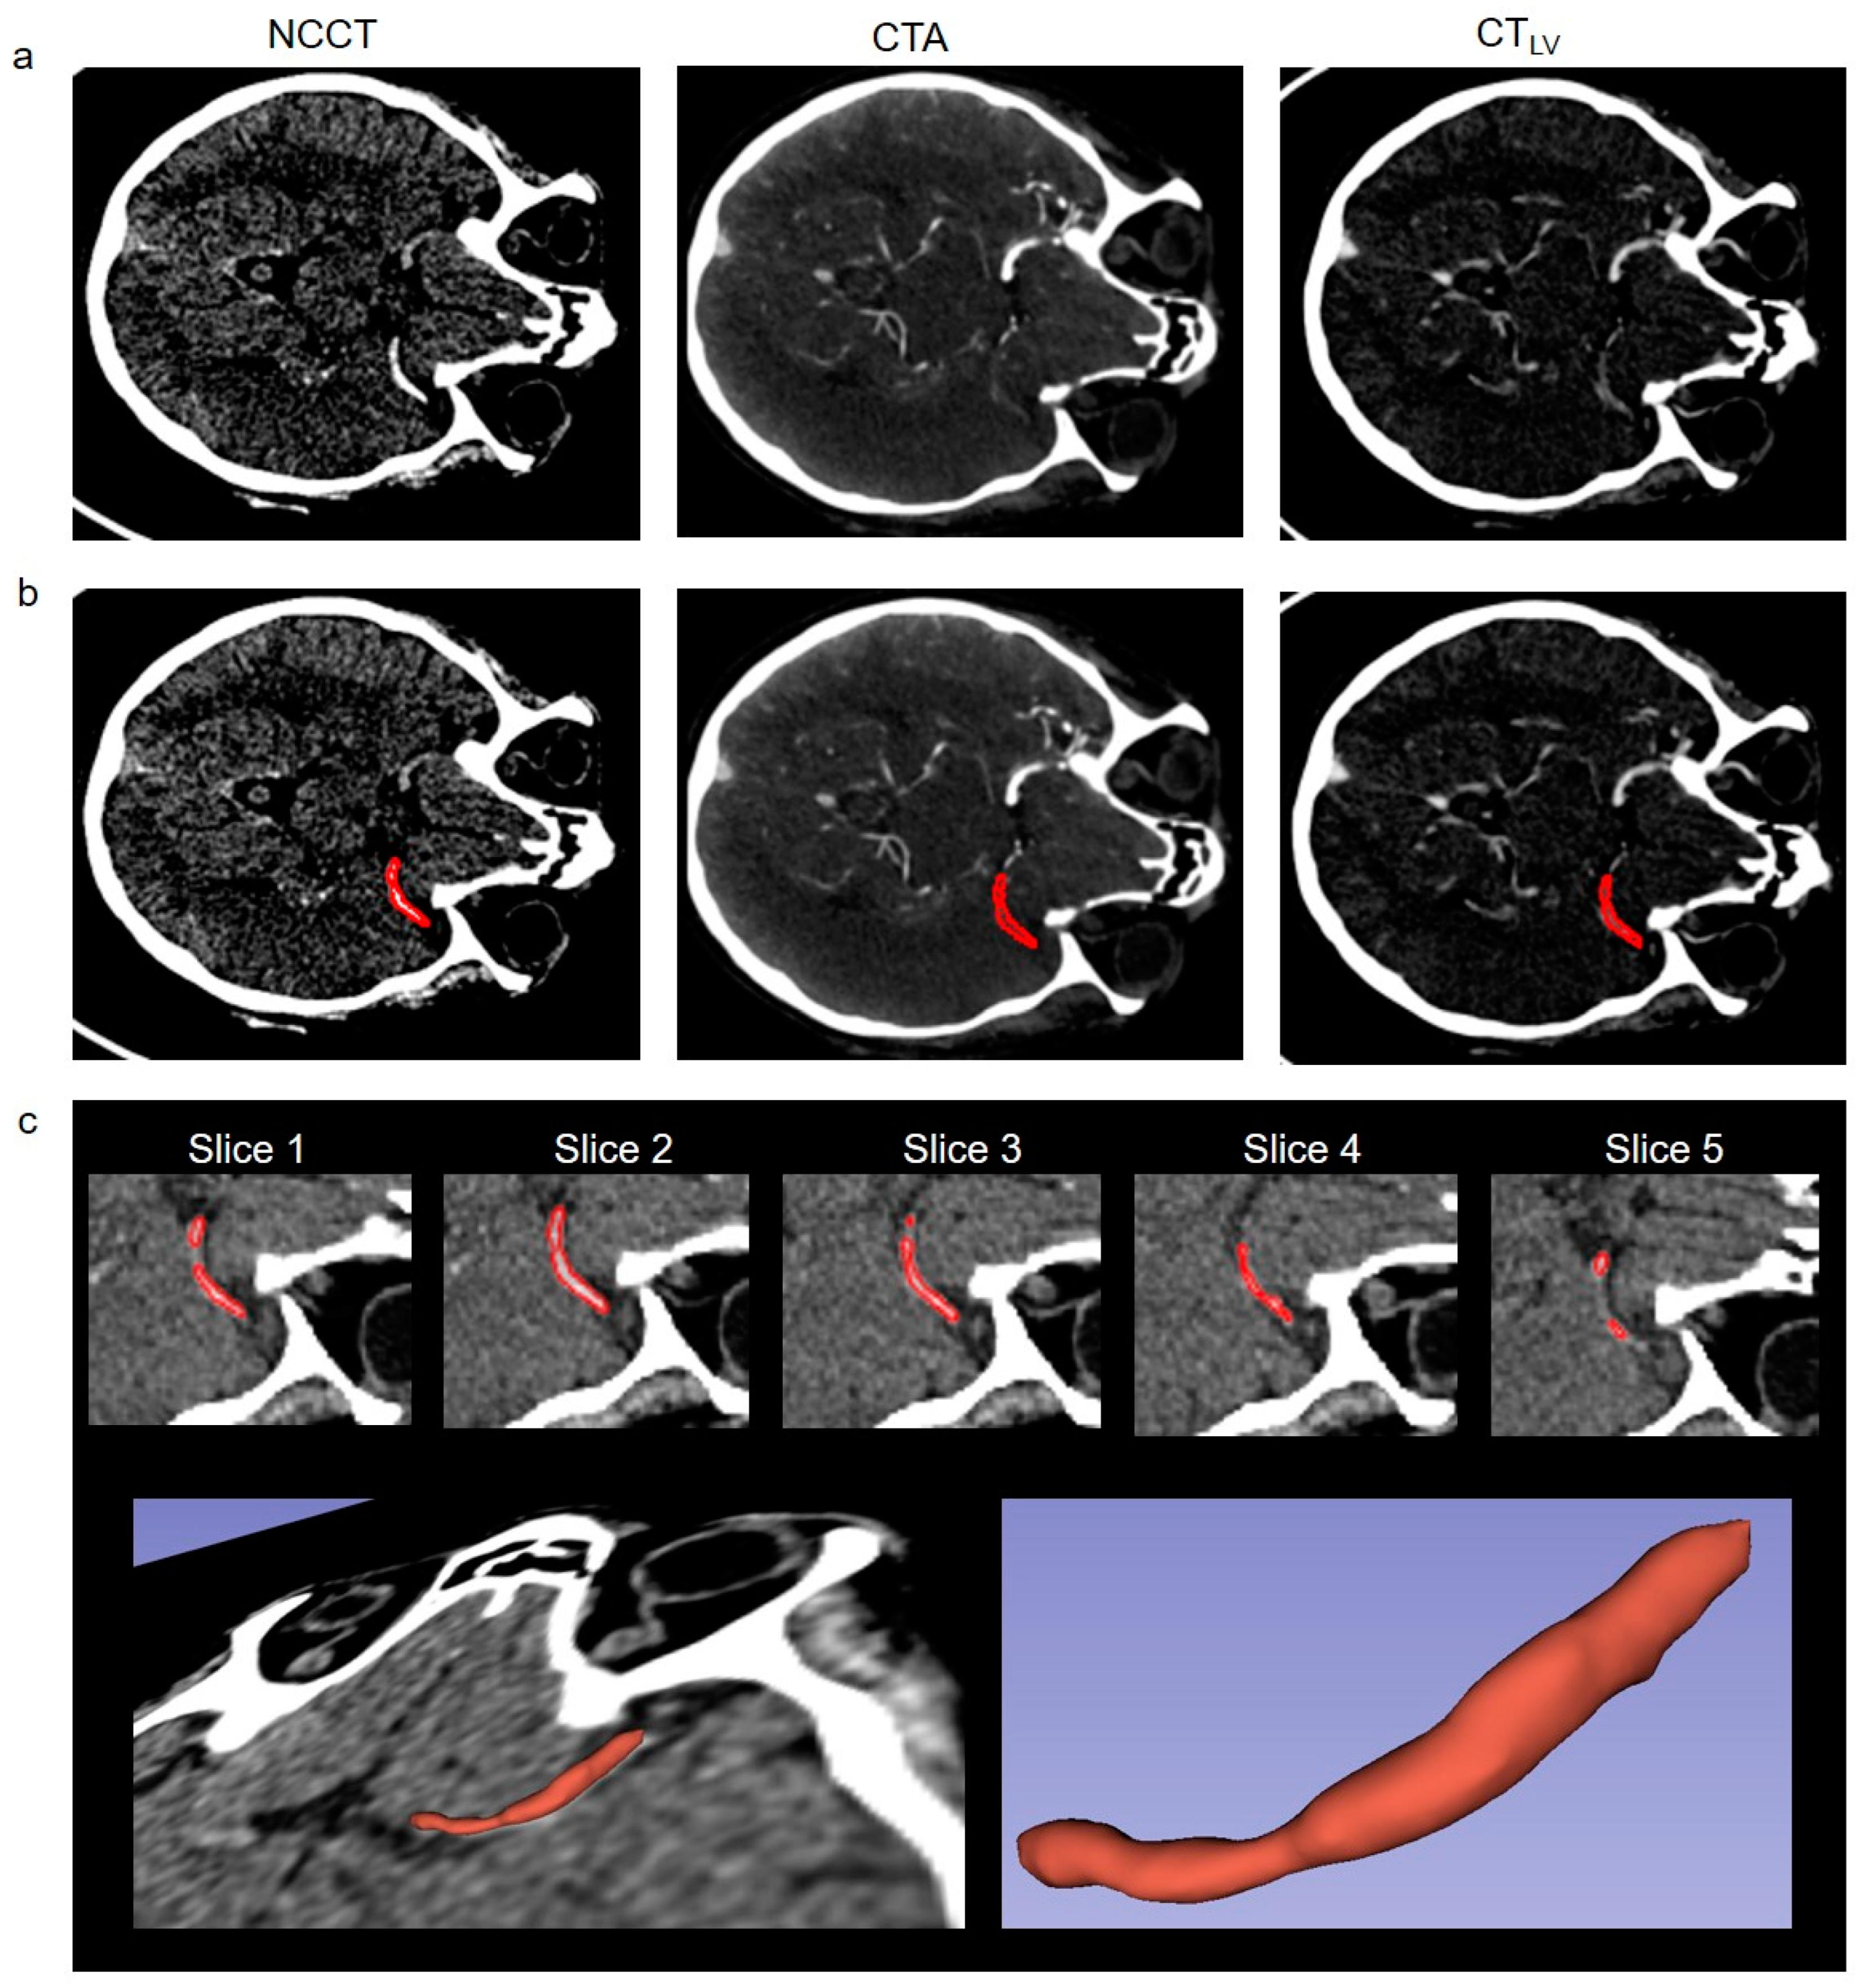

2.2. Imaging

2.3. Image Processing and Statistical Analysis